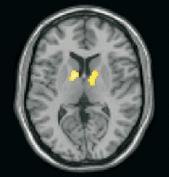

I risultati della ricerca di Cacioppo dimostrano che lo striato ventrale, regione del cervello associata alla ricompensa (reward), risulta molto più attivato in persone socialmente attive rispetto ai solitari durante la visione di immagini raffguranti persone in situazioni piacevoli. Al contrario, è la giunzione temporo-parietale, regione del cervello associata alla capacità di mettersi nella prospettiva di un’altra persona, ad essere molto meno attivata fra i solitari rispetto ai socialmente attivi, durante la visione di immagini di persone in situazioni spiacevoli.

Lo striato ventrale, che riveste un ruolo chiave nell’apprendimento, è una regione molto importante del cervello che viene attivata da gratificazioni primarie, quali il cibo, e secondarie, quali i soldi. Allo stesso modo, è stato dimostrato che anche gratificazioni sociali e il sentimento dell’amore possono attivare questa regione. Cacioppo studia da anni la solitudine e ha dimostrato in più occasioni che l’isolamento sociale può minacciare la salute di una persona, con effetti dannosi tanto quanto il fumo.

Nel nuovo studio Cacioppo e colleghi hanno dimostrato sia come la solitudine possa ridurre l’attività dello striato ventrale durante la visione di immagini di persone felici, sia come l’attività dello striato ventrale possa sollecitare il senso di solitudine. “E’ intrigante la possibilità che la solitudine possa risultare da una ridotta attività dello striato ventrale in risposta a ricompense sociali”, sostengono gli Autori.